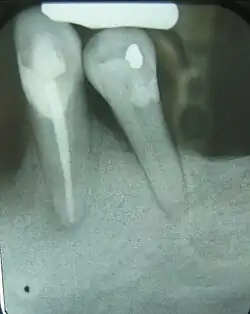

This X-ray film displays two lone-standing mandibular teeth, the lower left first premolar and canine, exhibiting severe bone loss of 30–50%. Widening of the periodontal ligament surrounding the premolar is due to secondary occlusal trauma.